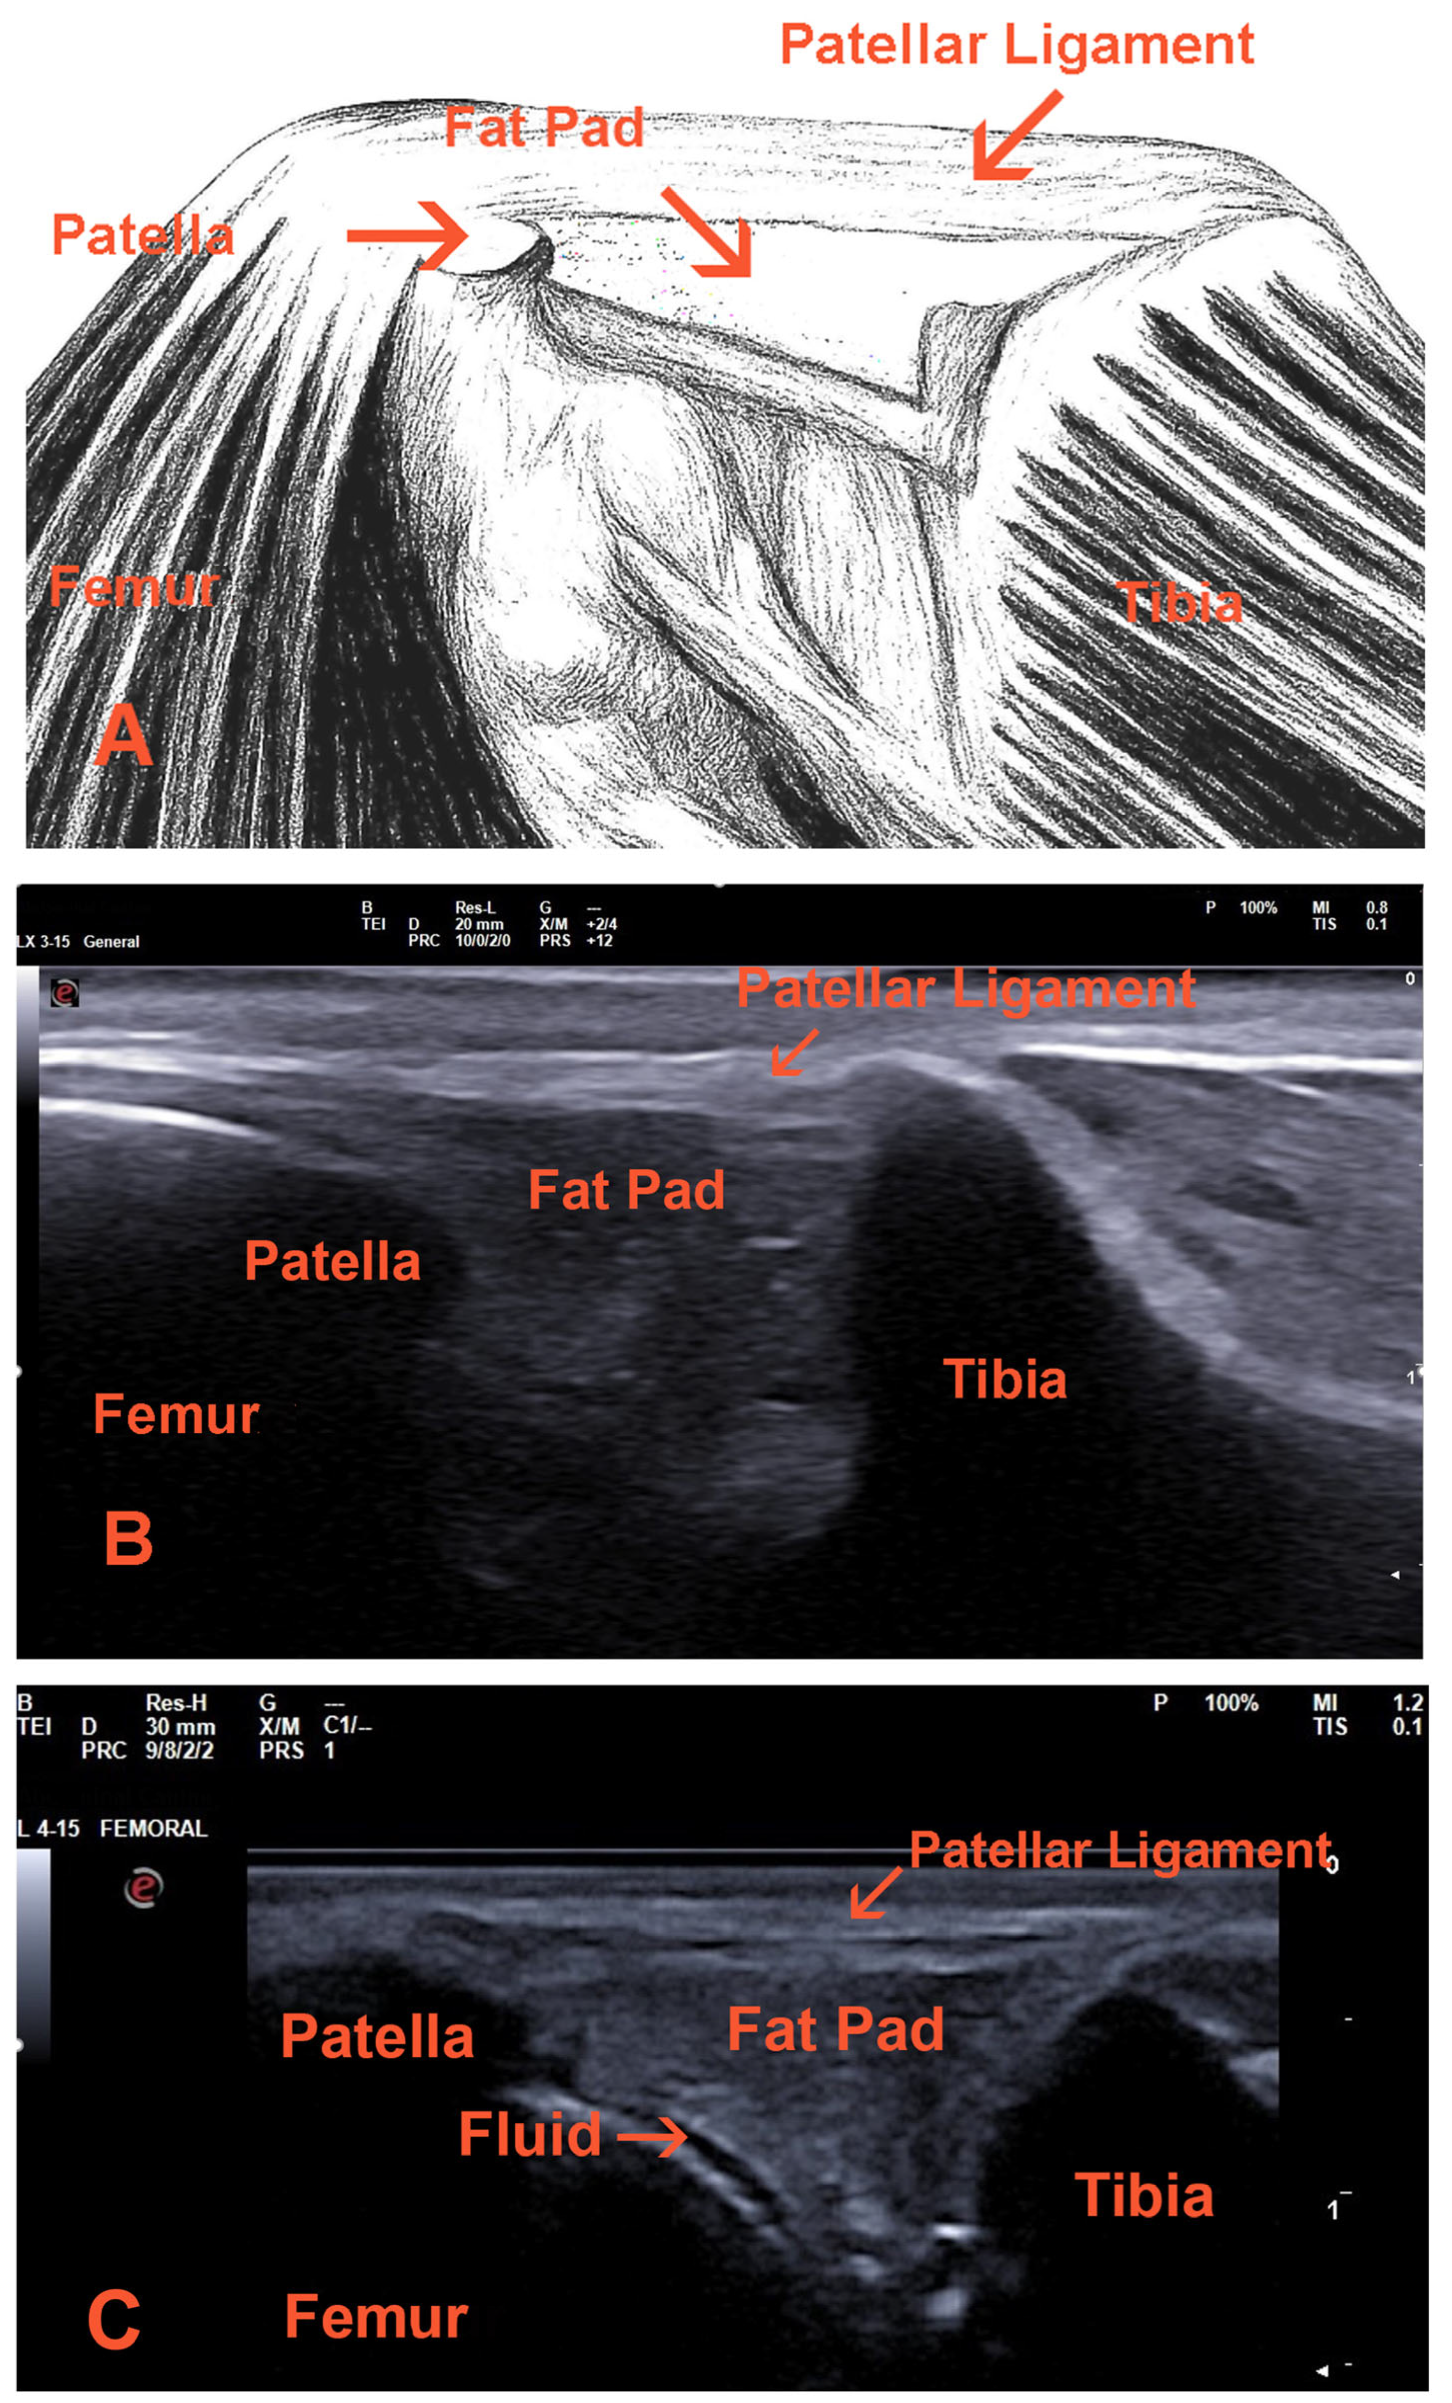

- Patellar ligament